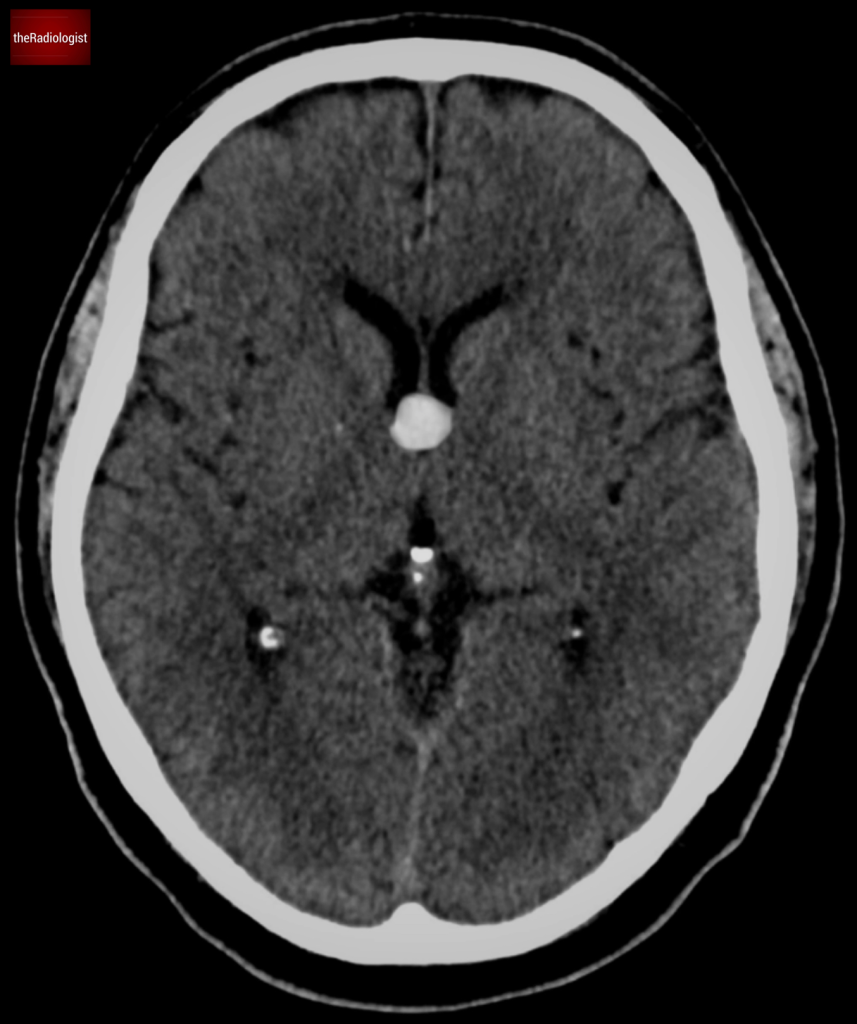

A colloid cyst is a benign epithelial-lined cyst that typically forms at the foramen of Monro. These cysts can be found incidentally on CT scans as small high-density regions in this area.

Colloid cysts usually show on CT as a high density lesion in the region of the foramen of Monro.

- On non contrast CT look for a well defined hyperdense lesion at the foramen of Monro.